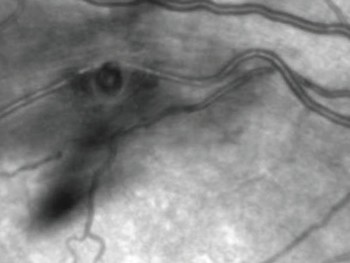

A Angiografia Fluoresceínica (AF), ou Angiofluoresceinografia, é um exame de grande importância no estudo das doenças que atingem a retina, coróide e nervo óptico. Doenças como Retinopatia Diabética, Degeneração Macular Relacionada à Idade (DMRI), Degenerações retininas hereditárias, Doenças oclusivas vasculares, entre outras, têm indicação para realizar esse exame, que apesar do nome complicado, é relativamente simples em sua realização, porém necessita grande experiência na área de retina e vítreo para a sua interpretação.

O exame é baseado na realização de fotografias do fundo de olho do paciente, após a injeção de um contraste, em uma veia do antebraço ou dorso da mão. As principais reações adversas que podem ocorrer, que não são freqüentes, são dor local se houver extravasamento do contraste, náuseas (5%) e vômitos (0.3%), mais comuns em jovens. Raras são reações alérgicas como coceira, vermelhidão local, edema de laringe, broncoespasmo, tromboflebite. São relatados casos raros de choque anafilático, infarto e até morte (0.0004%). O contraste é eliminado pelo organismo em torno de 24 horas, pelo fígado e rins, alterando a coloração da urina e pele nesse período. Deve –se evitar exposição solar por um período de 48 horas, para não haver reações urticariformes. O exame está contra-indicado em portadores de insuficiência renal, hepática e cardíaca não controlados, e em pacientes epilépticos. Após dilatação das pupilas com colírios, é feito o posicionamento do paciente no aparelho e injetado o contraste em cinco segundos. São realizados filmes e fotos seqüenciais são tiradas pelo oftalmologista, durando o exame de 5 a 10 minutos, conforme a doença estudada.